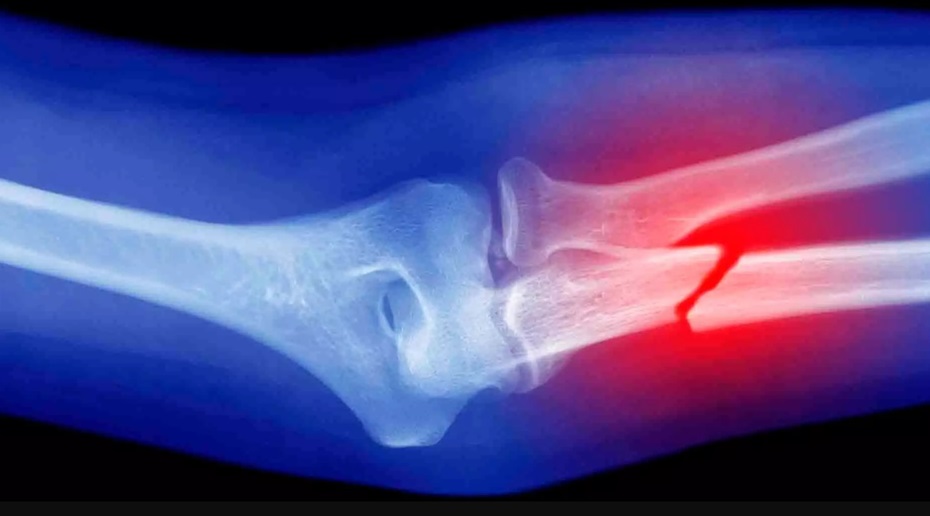

При лечении костей после переломов сращение травматических переломов костей происходит у большинства пострадавших по хондробластическому типу, т.е. через образование хрящевой костной мозоли. В этом процессе выделяют четыре фазы.

Развивается асептическое воспаление окружающих мягких тканей. Массивные кровоизлияния. Нарушается кровообращение в зоне перелома в виде стаза крови. Происходит выброс токсических продуктов в кровь, в окружающих перелом тканях повышается ферментативная активность. В концах отломков кости наблюдается некроз и микроизьеденность поверхности излома, никаких признаков сращения кости еще нет.